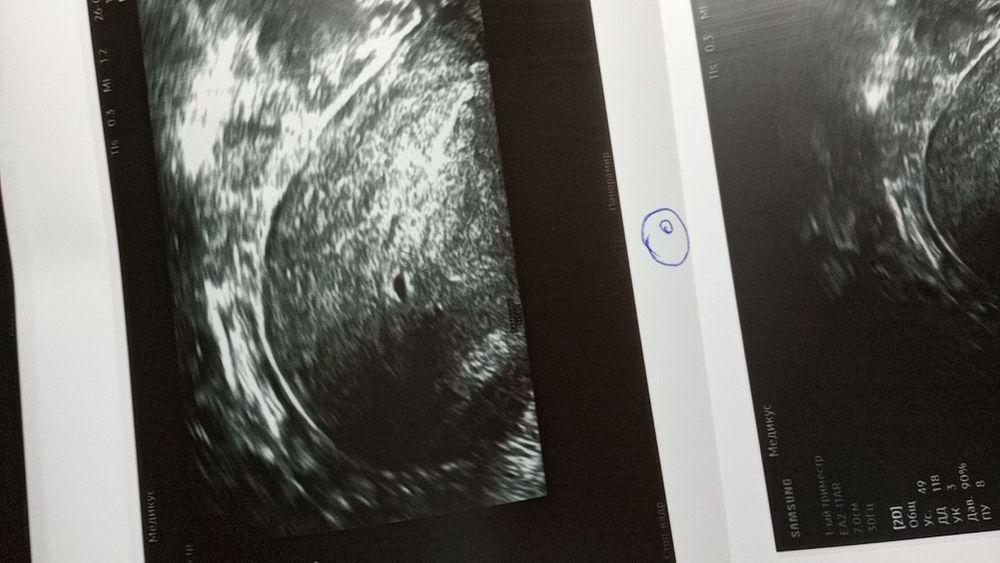

На УЗИ пятно 2 мм, диагноз : беременность 5-6 недель?

Заключение УЗИ :Беременность раннего срока?

Странно что тесты отрицательные. Но вообще очень похоже на плодное яйцо. Я бы не ждала и сдала хгч. Если он есть, то очевидно, что беременность есть.